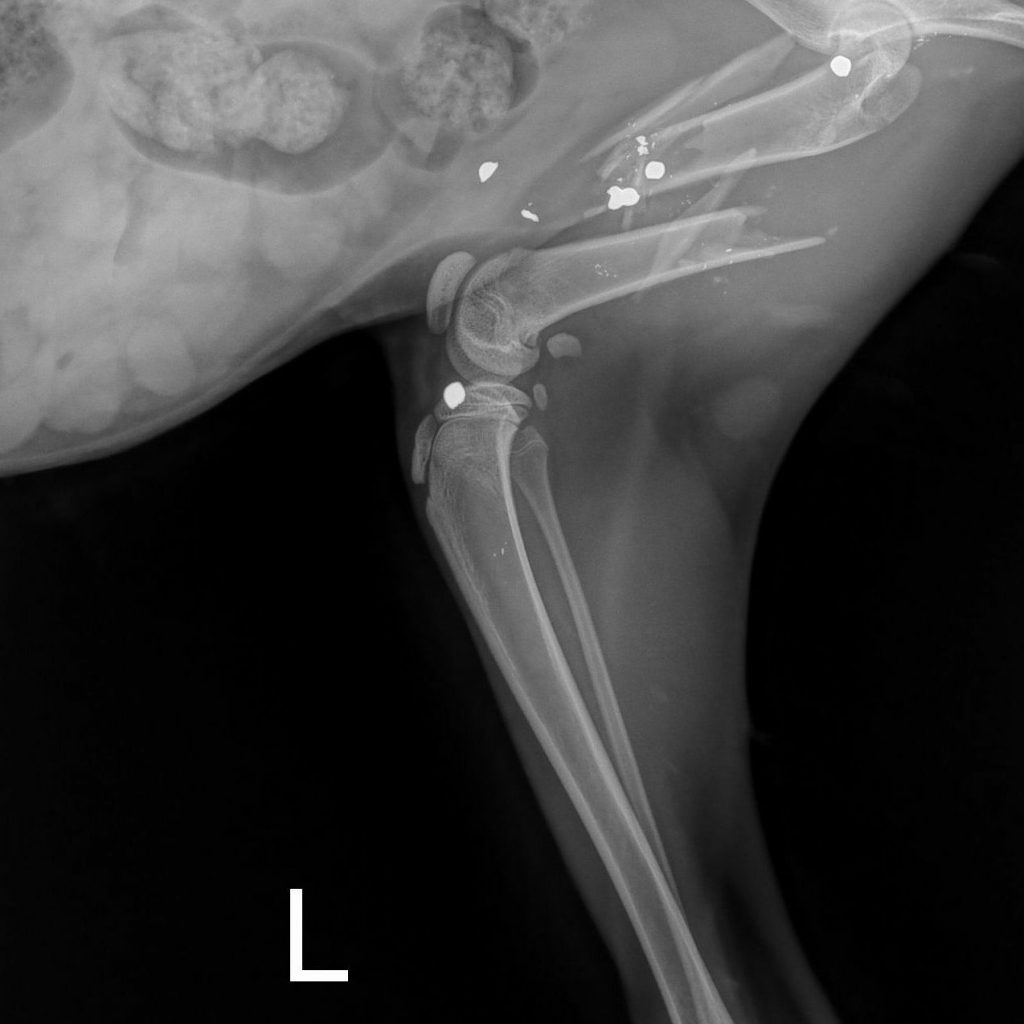

Today this cat arrived at the Richmond SPCA, and we named her Miracle. While Dr. David Molinas, our associate veterinarian, looked her over, she purred and made biscuits on the exam table with a level of affection that disguised the pain she must be experiencing. Radiographs from River Run Animal Hospital, where she was given supportive care yesterday, show metallic fragments that are likely birdshot scattered throughout her body, most highly concentrated in her pelvis and hind limbs. Both of her femurs, the large upper bones of the rear legs, are broken.

Though Dr. Molinas performs a number of complicated orthopedic surgeries for homeless animals we take in each year, Miracle's severe injuries require a specialist, and we have called upon Dr. Roy Barnes of James River Veterinary Surgery. Though the practice is normally closed on Fridays, Dr. Barnes and his surgical team agreed to take on Miracle's urgent case tomorrow. They hope to add a plate to her right femur, which has a single long fracture. Her left femur has broken into multiple pieces and will be more difficult to repair. Dr. Barnes will attempt to fix her left leg as well though we expect that healing will be challenging, and amputation of Miracle's rear leg remains a possibility.